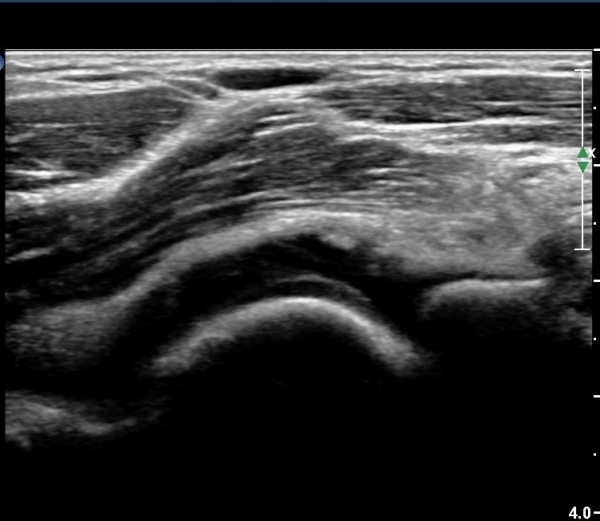

ÃÊÀ½ÆÄ °Ë»ç

ÆÈ²ÞÄ¡ ¾ÕÂÊ ¼ÒµÎ Á¾´Ü¸é°Ë»ç¿Í Ⱦ´Ü